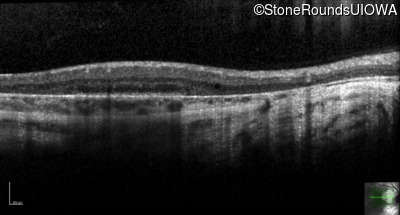

Optical Coherence Tomography - Left - 20/16

Exemplar / OCT Stack

OCT Stack